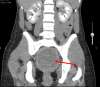

Vaginal agenesis is part of a group of anomalies, referred to as Mullerian anomalies due to their embryologic origin, in which there is a congenital absence of the vagina. We present a unique case in which a 20-year-old female presented to the Emergency Department with cyclical abdominal pain and primary amenorrhea. The original assessment showed a probable imperforate hymen; however, it was later found that she likely had vaginal agenesis. Vaginal agenesis is a rare disease, but it is prevalent enough that it should be kept at the forefront of the differential diagnosis in a woman with primary amenorrhea and recurring pain. We also highlight the importance of patient education in general, but categorically to sexual health.